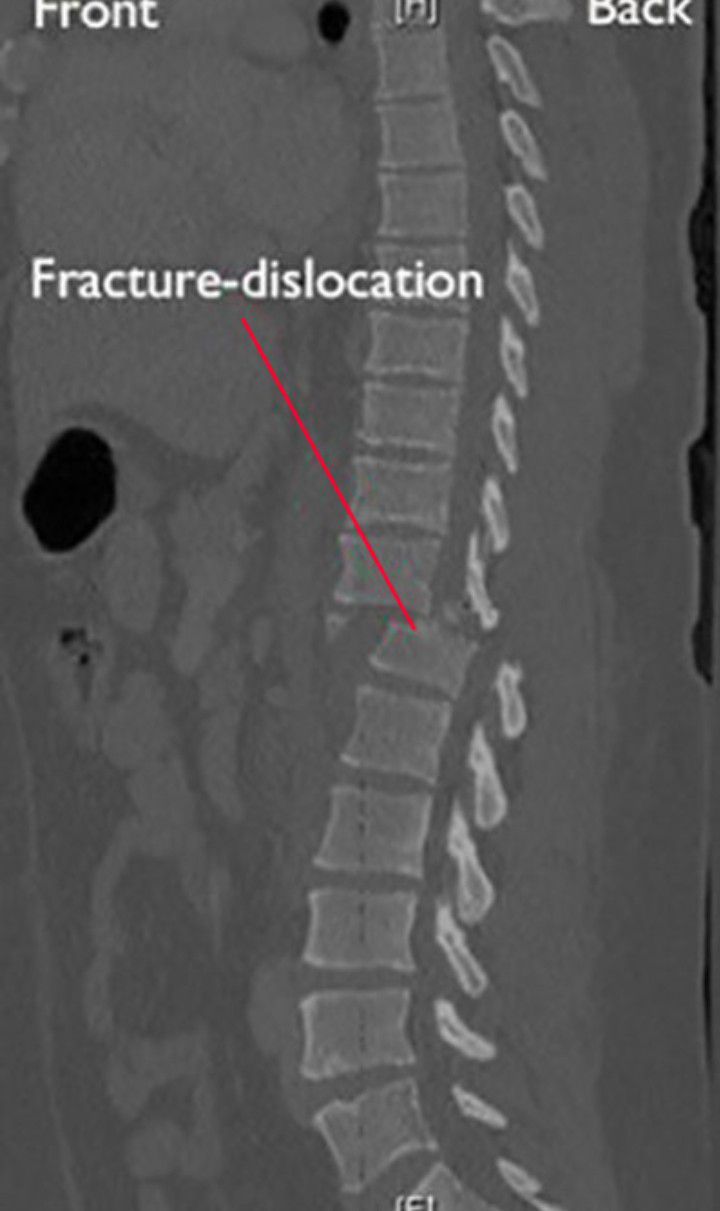

There are many different types of spinal fractures: Compression, Burst, Flexion-distraction, and Fracture-dislocation. Each of these types of fractures are described. Other terms your doctor may use to describe a fracture include stable, unstable, minor, and/or major. Fracture–dislocation, a severe injury in which both fracture and dislocation take place simultaneously. Frequently, a loose piece of bone remains jammed between the ends of the dislocated bones and may have to be removed surgically before the dislocation can be reduced.